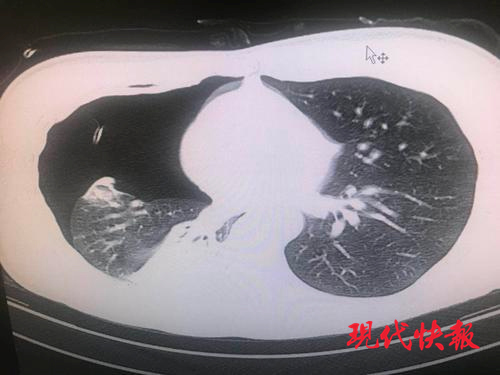

△小陈的肺部 CT,可以看到其肺部气胸严重。

结果胸片检查显示,小陈右侧大量肺泡破裂导致气胸,肺部被压缩了 70% 以上。